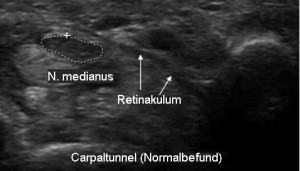

Da die neurologische Untersuchung, insbesondere zu Beginn der Beschwerden häufig keine auffälligen Befunde liefert, wird die Diagnose in der Regel mittels Messung der elektrischen Leitfunktion des Nervens gestellt. Durch die Entwicklung hochauflösender Ultraschallgeräte ist es heutzutage jedoch möglich eine sehr gute und verlässliche Darstellung von Nerven zu ermöglichen, so dass diese Methode nun auch in der Diagnostik des Karpaltunnel-Syndroms eingesetzt werden kann.

Die Ultraschalluntersuchung kann die Kompression und die dadurch hervorgerufene Schwellung des Nervens vor dem Engpass nachweisen und hat eine gleichwertige Aussagekraft und Zuverlässigkeit wie die elektrische Nervenmessung erreicht. Die Kombination beider Methoden erhöht die Treffsicherheit der korrekten Diagnose noch einmal, insbesondere bei leichten Befunden und nach vorherigen Operationen am Karpaltunnel. Ein weiterer Vorteil ist die Darstellung von Lagevarianten von Nerven, Sehnen, Muskeln und Gefäßen oder besonderen Strukturen im Karpaltunnel, so dass der Handchirurg optimierte Information vor einer evtl. notwendigen Operation erhält.